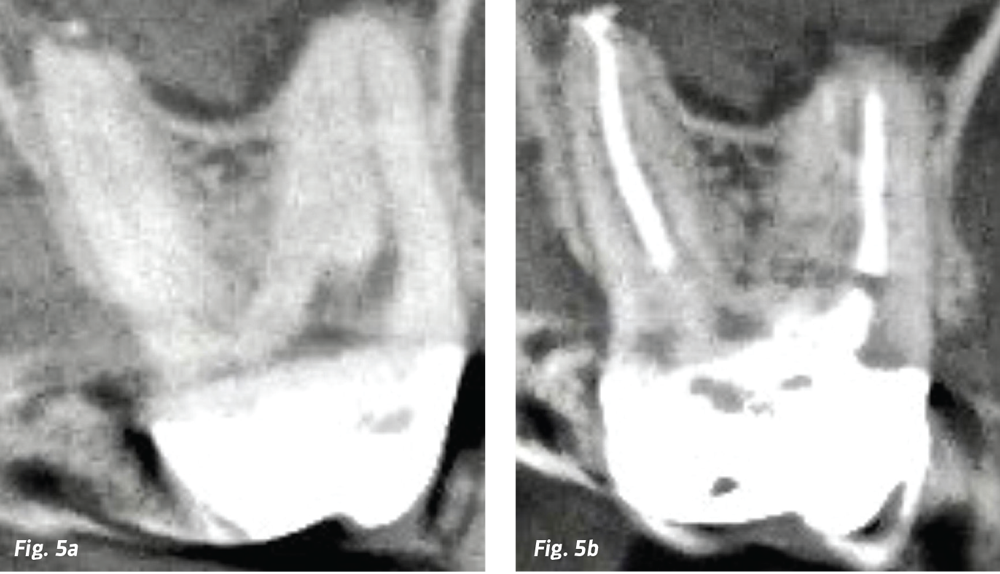

Fig. 3a: Mesial CBCT view of an MB root of a maxillary molar after a fruitless search for the MB2 canal. Note the 4mm-long MB2 canal that bifurcates midroot off the MB1 canal, makes a 90-degree turn, and exits. Cementing a single gutta percha cone with BC Sealer without a downpack won’t fill this anatomy. Fig. 3b: Postoperative CBCT shows MB2 filled with a shortened CW downpack.

Fig. 5a: Master gutta percha points cemented in canals with BC HiFlow Sealer. Note the short apical lateral canals filled just by cementing a single gutta percha cone in the palatal root; also note the incomplete lateral fill of the MB root complex (left). Fig. 5b: Continuous wave electric heat plugger in its final position after a modified CW downpack to midroot. Note the MB2 and MB3 complexities filled by bioceramic sealer after the shortened hydraulic wave of condensation (right).

If BC Sealer fills lateral canals 1–2mm in length when doing single-cone obturation, why do we need to heat gutta percha up and downpack at all? Unfortunately, lateral canal spaces in molars are way bigger than that. Forget about the 4mm wide isthmus forms found in mesial roots of lower molars. Forget about the fins, webs, loops and lateral canals that commonly project off single primary canals. Be worried about MB2 and MB3 canals in upper molars that bifurcate midroot off the MB1, turn 90 degrees and bifurcate before exiting (Figs. 3a and 3b, p. 73). These can be 7–8mm in length, so for me, I’m still a warm gutta percha guy. No longer do I have to work as hard to get the 3D results I expect to see on postobturation radiographs. (Fig. 4)